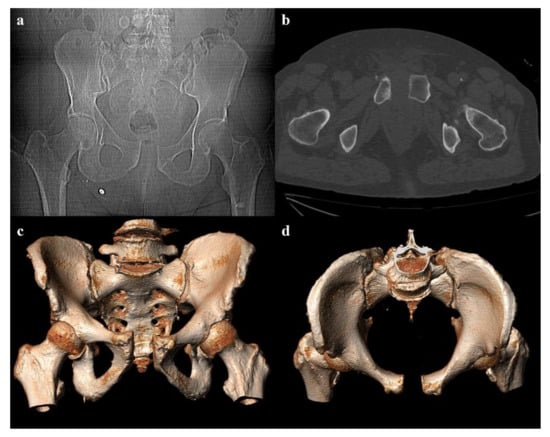

Figure 5. Anterior–posterior compression fracture, type 2. Axial CT images (a,b) show a pubic symphysis diastasis of 3.2 cm, and an anterior sacroiliac joint diastasis on the left side. Three-dimensional volume-rendering CT reconstructions in outlet and inlet views (c,d) confirm the findings.

• Grade 2: pubic symphysis diastasis >2.5 cm, possible vertical fracture of the pubic rami, and anterior sacroiliac joint diastasis (Figure 5). The anterior sacroiliac joint diastasis is due to the rupture of the anterior sacroiliac ligament, sacrospinous ligament, and sacrotuberous ligament. Anterior–posterior compression grade 2 injuries have a rotational instability and require a stable internal fixation [3].